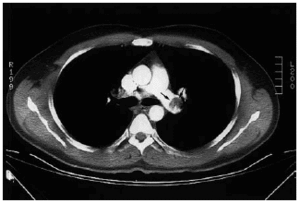

Se le practicó tomografía axial computarizada (TAC) helicoidal, que demostró la presencia de trombos en la luz del tronco principal de la arteria pulmonar derecha (fig. 1) y en la rama inferior de la arteria pulmonar izquierda (fig. 2).

Fig. 1.